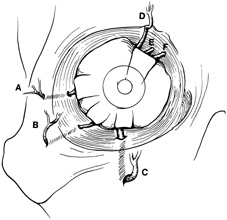

to the rim (Fig. 7). Transecting the neurovascular bundles results in a small area of

surface of the lateral rim.  Fig. 7. Coronal schematic view demonstrating major vessels penetrating periorbita

and traversing the extraperiosteal space that may be encountered during

periorbital elevation. (A, zygomaticotemporal artery; B, zygomaticofacial artery; C, communicating branch of infraorbital artery: D, supraorbital artery: E, posterior ethmoidal artery: F, anterior ethmoidal artery.) Fig. 7. Coronal schematic view demonstrating major vessels penetrating periorbita

and traversing the extraperiosteal space that may be encountered during

periorbital elevation. (A, zygomaticotemporal artery; B, zygomaticofacial artery; C, communicating branch of infraorbital artery: D, supraorbital artery: E, posterior ethmoidal artery: F, anterior ethmoidal artery.)

|